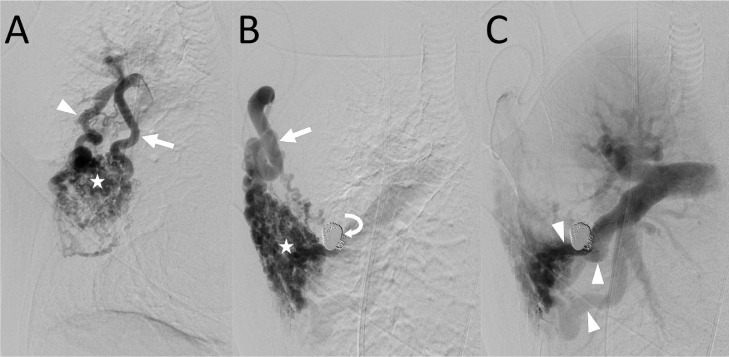

Fig. 2.

Angiography of 2 main feeders of the systemic artery-to-pulmonary artery (PA) vascular malformation (VM) of the right chest wall. (A) Angiography of the right internal thoracic artery (arrow) shows the VM (star) and a drainer (arrowhead) connected to the PA segment 3 (A3). (B) Angiography of the pectoral branch (arrow) at the arterial phase shows the VM (star). Coils (curved arrow) placed for embolization of the drainer connected to the A3 are observed. (C) Angiography of the pectoral branch at the late arterial phase shows drainers (arrowheads) connected to the A4, A5, and A8. The right PA is retrogradely opacified.